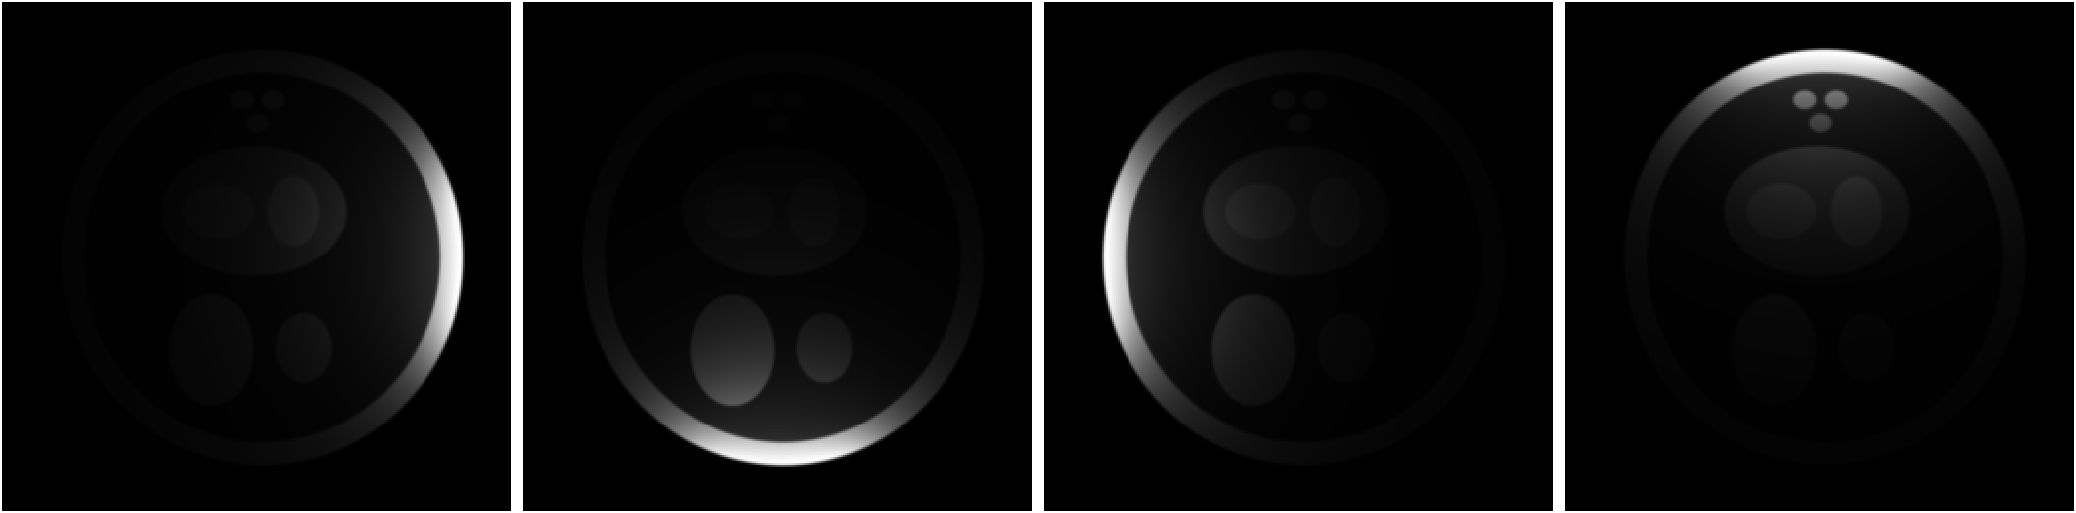

In this study, we illustrate how SCC can improve the fidelity of the reconstructed image using a digital phantom. To this end, we simulated a image, , depicted in Fig. 2. The true sensitivity maps from four surface coils were generated using the Biot-Savart law. The coils were assumed to be circular wire loops, with a radius that is 20% of the FOV, with the cylindrical axes of the coils pointing towards the center of the image. The true sensitivity maps were element-wise multiplied with to generate individual coil images. Using SSoS as sensitivity maps, the image, , was recovered using SENSE. As shown in the Fig. 3d, exhibits significant intensity variation, with the center of the image appearing dark. One could adjust the image intensity by histogram manipulation, but such measures do not fully address the problem. The true sensitivity maps (not shown) of two larger body coils, each with a radius equal to the FOV, were also generated using the Biot-Savart law. To simulate pre-scan, low-resolution data comprising of center of k-space were generated from both four small surface coils () and two large body coils (). Following the procedure described in the previous section, two correction maps were constructed using SCC. However, the interpolation step was skipped because the digital phantom is already 2D. The last row in Fig. 3 shows , , , and . Both and show marked improvement in the uniformity of image intensity. The normalized mean squared error (NMSE) defined as was dB, dB, and dB for , , and , respectively. The NMSE of or is primarily limited by the uniformity of , which, in turn, depends on the body-coil size.